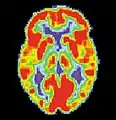

Maladie d'Alzheimer

La maladie d'Alzheimer (MA) est une maladie cérébrale progressive, dégénérative et fatale, dans laquelle est recensée une perte importante des cellules. Par conséquent, la mort des cellules cérébrales survient, bien que cette maladie soit la forme de démence la plus répandue[10]. À travers le monde, il existe 1 à 5 % de la population atteinte de la maladie d'Alzheimer[11]. Il est estimé que 500 000 Canadiens souffrent actuellement de la maladie d'Alzheimer ou d'une autre démence liée. Elle est la cause de handicap la plus répandue chez les individus âgés de 65 ans ou plus[10]. Les femmes sont disproportionnellement atteintes par cette maladie[12].